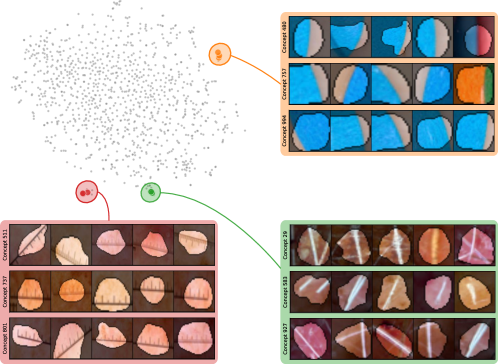

Model Perspective

Next, we apply bias identification approaches from the model perspective by identifying outlier neurons based on activation pattern via DORA and relevance pattern by clustering pair-wise cosine distances between concept relevance scores. We focus on latent activations and relevances after the third residual block. DORA uses a distance function based on how neurons activate upon each others n-AMS, achieving high similarity when neurons activate upon similar input signal. A 2D visualization of the resulting distance matrix is shown in Fig. 6 (bottom left). Identified outlier concepts include ruler () and (white) hair (). We further compute pairwise cosine distances between latent relevance scores , aggregated over spatial dimensions, and apply UMAP to embed the resulting distance matrix in . This results in high similarity between neurons (concepts) that the model uses similarly for predictions. The concept clustering is visualized in Fig. 6 (bottom right), highlighting two outlier clusters focused on rulers () and blueish tint ().

Results for other classes, model architectures, and datasets are presented in Appendix A.6.1. This includes experiments with ECG data in Fig. 10, revealing the artificially inserted static noise in the attacked lead from both data and model perspectives. Notably, dominant spurious concepts, such as the artificial timestamp in HyperKvasir or the static noise in PTB-XL, may not be detected as outlier concepts. In such cases, analyzing prediction sub-strategies via PCX may provide additional insights on spurious inlier behavior. Hard-to-interpret concept representations pose another challenge for the model perspective. For example, the brightness artifact in CheXpert is not clearly visible in the concept UMAP (see. Fig. 15, right), but can easily be detected using SpRAy (Fig. 15, left) or PCX (Fig. 22). In summary, while all considered spurious features are detected, the choice of bias identification approach is crucial, as some shortcuts are easier to detect as outlier concept (e.g., ruler) and others via PCX (e.g., brightness, static noise in ECG).